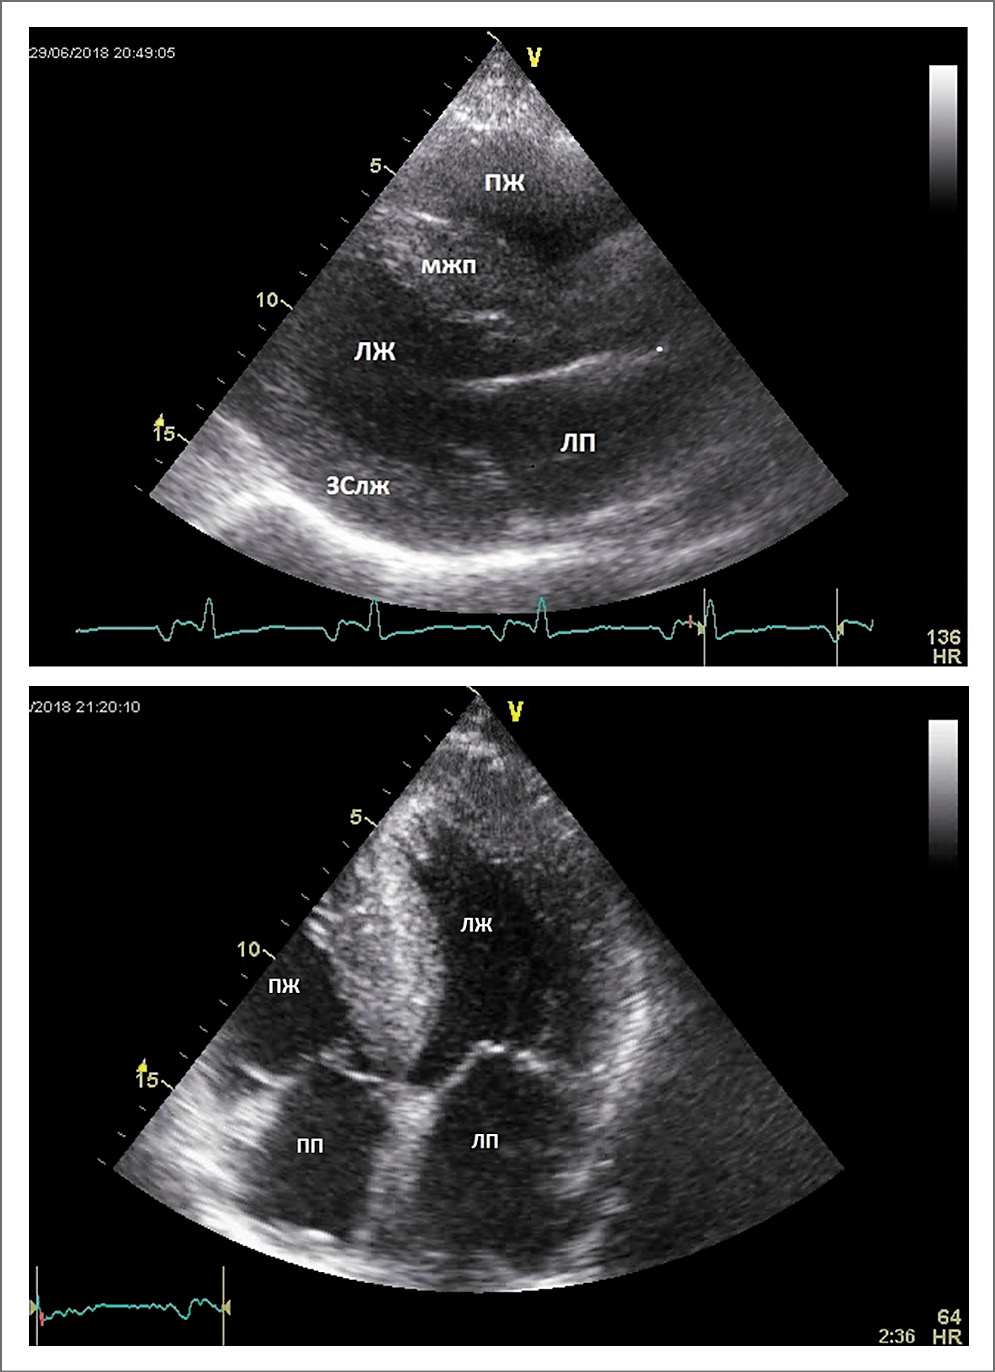

Данные ЭхоКГ представлены в табл. 1 и на рис. 2–5.

Рис. 2. ЭхоКГ пациента (парастернальная длинная ось ЛЖ и апикальное 4-камерное изображение)

Как представлено в табл. 1 и на рис. 2, при ЭхоКГ-исследовании обнаружено:

- гипертрофия миокарда ЛЖ и ПЖ, индекс массы миокарда ЛЖ 261 г/м2, толщина межжелудочковой перегородки (МЖП) 24 мм, толщина задней стенки ЛЖ (ЗСЛЖ) 18 мм → 24 мм, МЖП/ЗСЛЖ 1,33–1,0, что соответствует ГКМП-фенотипу. Размер полости ЛЖ не увеличен. Дилатация обоих предсердий (предсердно-желудочковое отношение 1,09–1,22), что соответствует осложненному ремоделированию, смешанный фенотип (ГКМП + рестриктивная кардиомиопатия – РКМП);

- прогрессирующая систолическая дисфункция ЛЖ (фракция выброса – ФВ ЛЖ: 47%→33%→28%). МЖП обращена выпуклостью в сторону ЛЖ. Нарастание толщины передней стенки ПЖ – ПСПЖ (4 мм → 10 мм → 11 мм). Расчетное систолическое давление в легочной артерии умеренно повышено (55–57 мм рт. ст.). Дилатация ПЖ. Выявлено небольшое количество свободной жидкости в полости перикарда;

- митральная и трикуспидальная регургитация 1–2 степени, незначительная приклапанная аортальная регургитация;

- выраженная диастолическая дисфункция ЛЖ: рестриктивный тип наполнения ЛЖ (повышено конечно-диастолическое давление ЛЖ), Е/e’=35; максимальная скорость трикуспидальной регургитации 3,2 м/с (см. рис. 3, 4).

Резко снижена систолическая скорость движения кольца митрального клапана, низкие показатели деформации ЛЖ (средний 2D-strain=-4,4%, в большей степени нарушение кинетики задней, боковой и передней стенок ЛЖ, в меньшей степени снижены показатели деформации верхушки ЛЖ). Систолическая дисфункция ПЖ: TAPSE – 16 мм, TAVS – 7–8 см/с.